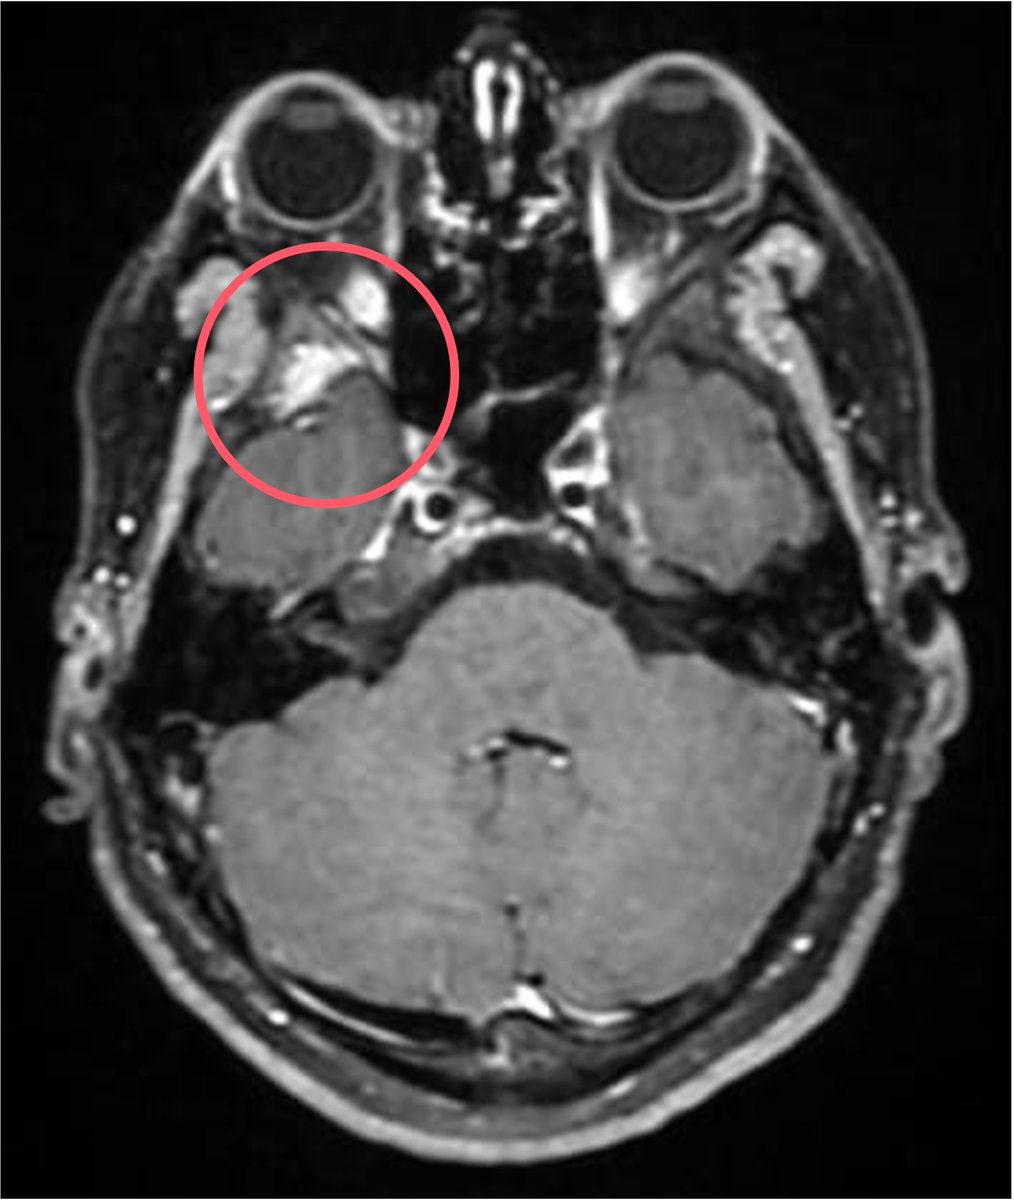

21 y/M 2018 - headache, LOW, low grade fever.Imaging had seller mass lesion for which referred to higher centre (didn't follow up). 2020 - Additiona